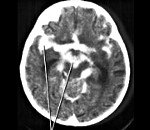

• МРТ/КТ головного мозга. Могут не выявлять патологических изменений, позволяют исключить объёмные образования (кисты, абсцессы, церебральные опухоли). Более информативна МРТ головного мозга с контрастированием, визуализирующая воспалительные очаги по накоплению контраста.